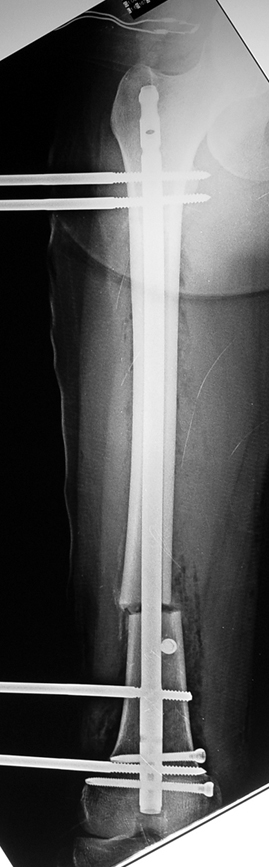

İntramedüller çivinin yerleştirilmesi ve osteotomi: Hasta traksiyon masasına supin pozisyonda yatırılır ve sağlam bacak altta olacak şekilde bacaklar makas pozisyonuna alınır. Standart yolla piriformis çukurundan medulla içine girilir ve kılavuz tel üzerinden kullanılacak çividen 1.5 mm daha kalın oyucu ile medulla oyulur. Proksimal femur, çivinin proksimali daha kalın olduğu için daha kalın oyulur. Radyografide osteotomi hattı planlaması yapılır. Planlama yapılırken uzatma sonunda distalde en az 8 cm. çivi kalması stabilizasyon için gereklidir. Kortikotomi perkütan olarak kortikotom ile tamamlanır. Daha sonra kılavuz tel çivinin boyunu ölçmek için distale ilerletilir. Uygun boyda intramedüller çivi çakılır. Son olarak çivi proksimalden kilitlenir ve bir adet dren konarak ameliyatın birinci kısmı tamamlanır.

Eksternal fiksatör uygulanımı: İntramedüller çiviye değmeden aşağıya ve yukarıya üçer adet Schanz vidası gönderilir. Vidalarla çivi arasında en az 1 mm den fazla mesafe olmalıdır.

Biz son zamanlarda, seçilmiş vakalarda, uzatma sonrası uzunluğu ve “alignment’ı” korumak amacı ile unilateral dinamik aksiyel fiksatör ve kilitli intramedüller çivi kombinasyonunu tercih etmekteyiz. Bu yöntemin ön şartları medullanın en dar çapının 7 mm.’den geniş olması ve uzatma sonrası distalde en az 8 cm. uzunluğunda çivi kalabilmesidir. İntramedüller çivi hem uzatma esnasında femurun üzerine gelen makaslama ve bükülme kuvvetlerini nötralize etmekte hem eksternal fiksasyon süresini kısaltmakta, hem de yeni oluşan kemiği kırıklara karşı korumaktadır. Serimizde bir vakada subtrokanterik femoral osteotomi yapılmıştır. İntramedüller çiviye rağmen varus angulasyonu oluşması yönünde bir dezavantaj tespit etmedik.

İlizarov, distraksiyon osteogenezisi için endosteal kan dolaşımının önemini vurgulamıştır. Biz tüm vakalarımızda femuru oyarak intramedüller çiviyi çaktık; buna rağmen hiçbir vakada kallus oluşma süresi tahminimizden daha uzun olmadı. Bu yüzden medüller dolaşımın bozulmasına bağlı yeni kemik oluşma hızında bir yavaşlama olmadığını düşünüyoruz. Oyma sonrası meydana gelen revaskülarizasyon, intramedüller çivili fiksasyon stabilitesi ve erken fonksiyonel yüklenme bu gerçeğin temelini oluşturmaktadır. Eksternal ve internal fiksasyon yöntemlerinin kombine kullanımının potansiyel dezavantajları kan kaybının artması, intramedüller infeksiyon, yağ embolisi olasılığı ve aşırı metal yüküdür. Bunların içinde en çok korkulan problem bir çivi dibi infeksiyonun tetikleyeceği derin intramedüller infeksiyondur (panosteomyelit). Bizim serimizde bu yönde hiçbir komplikasyon gelişmemiştir. Bu olası komplikasyonun önlenmesi amacı ile uzatma sonundaki kilitleme medialden yapılmalıdır; ayrıca intramedüller çivi ve eksternal fiksasyon pinlerinin teması önlenmelidir.